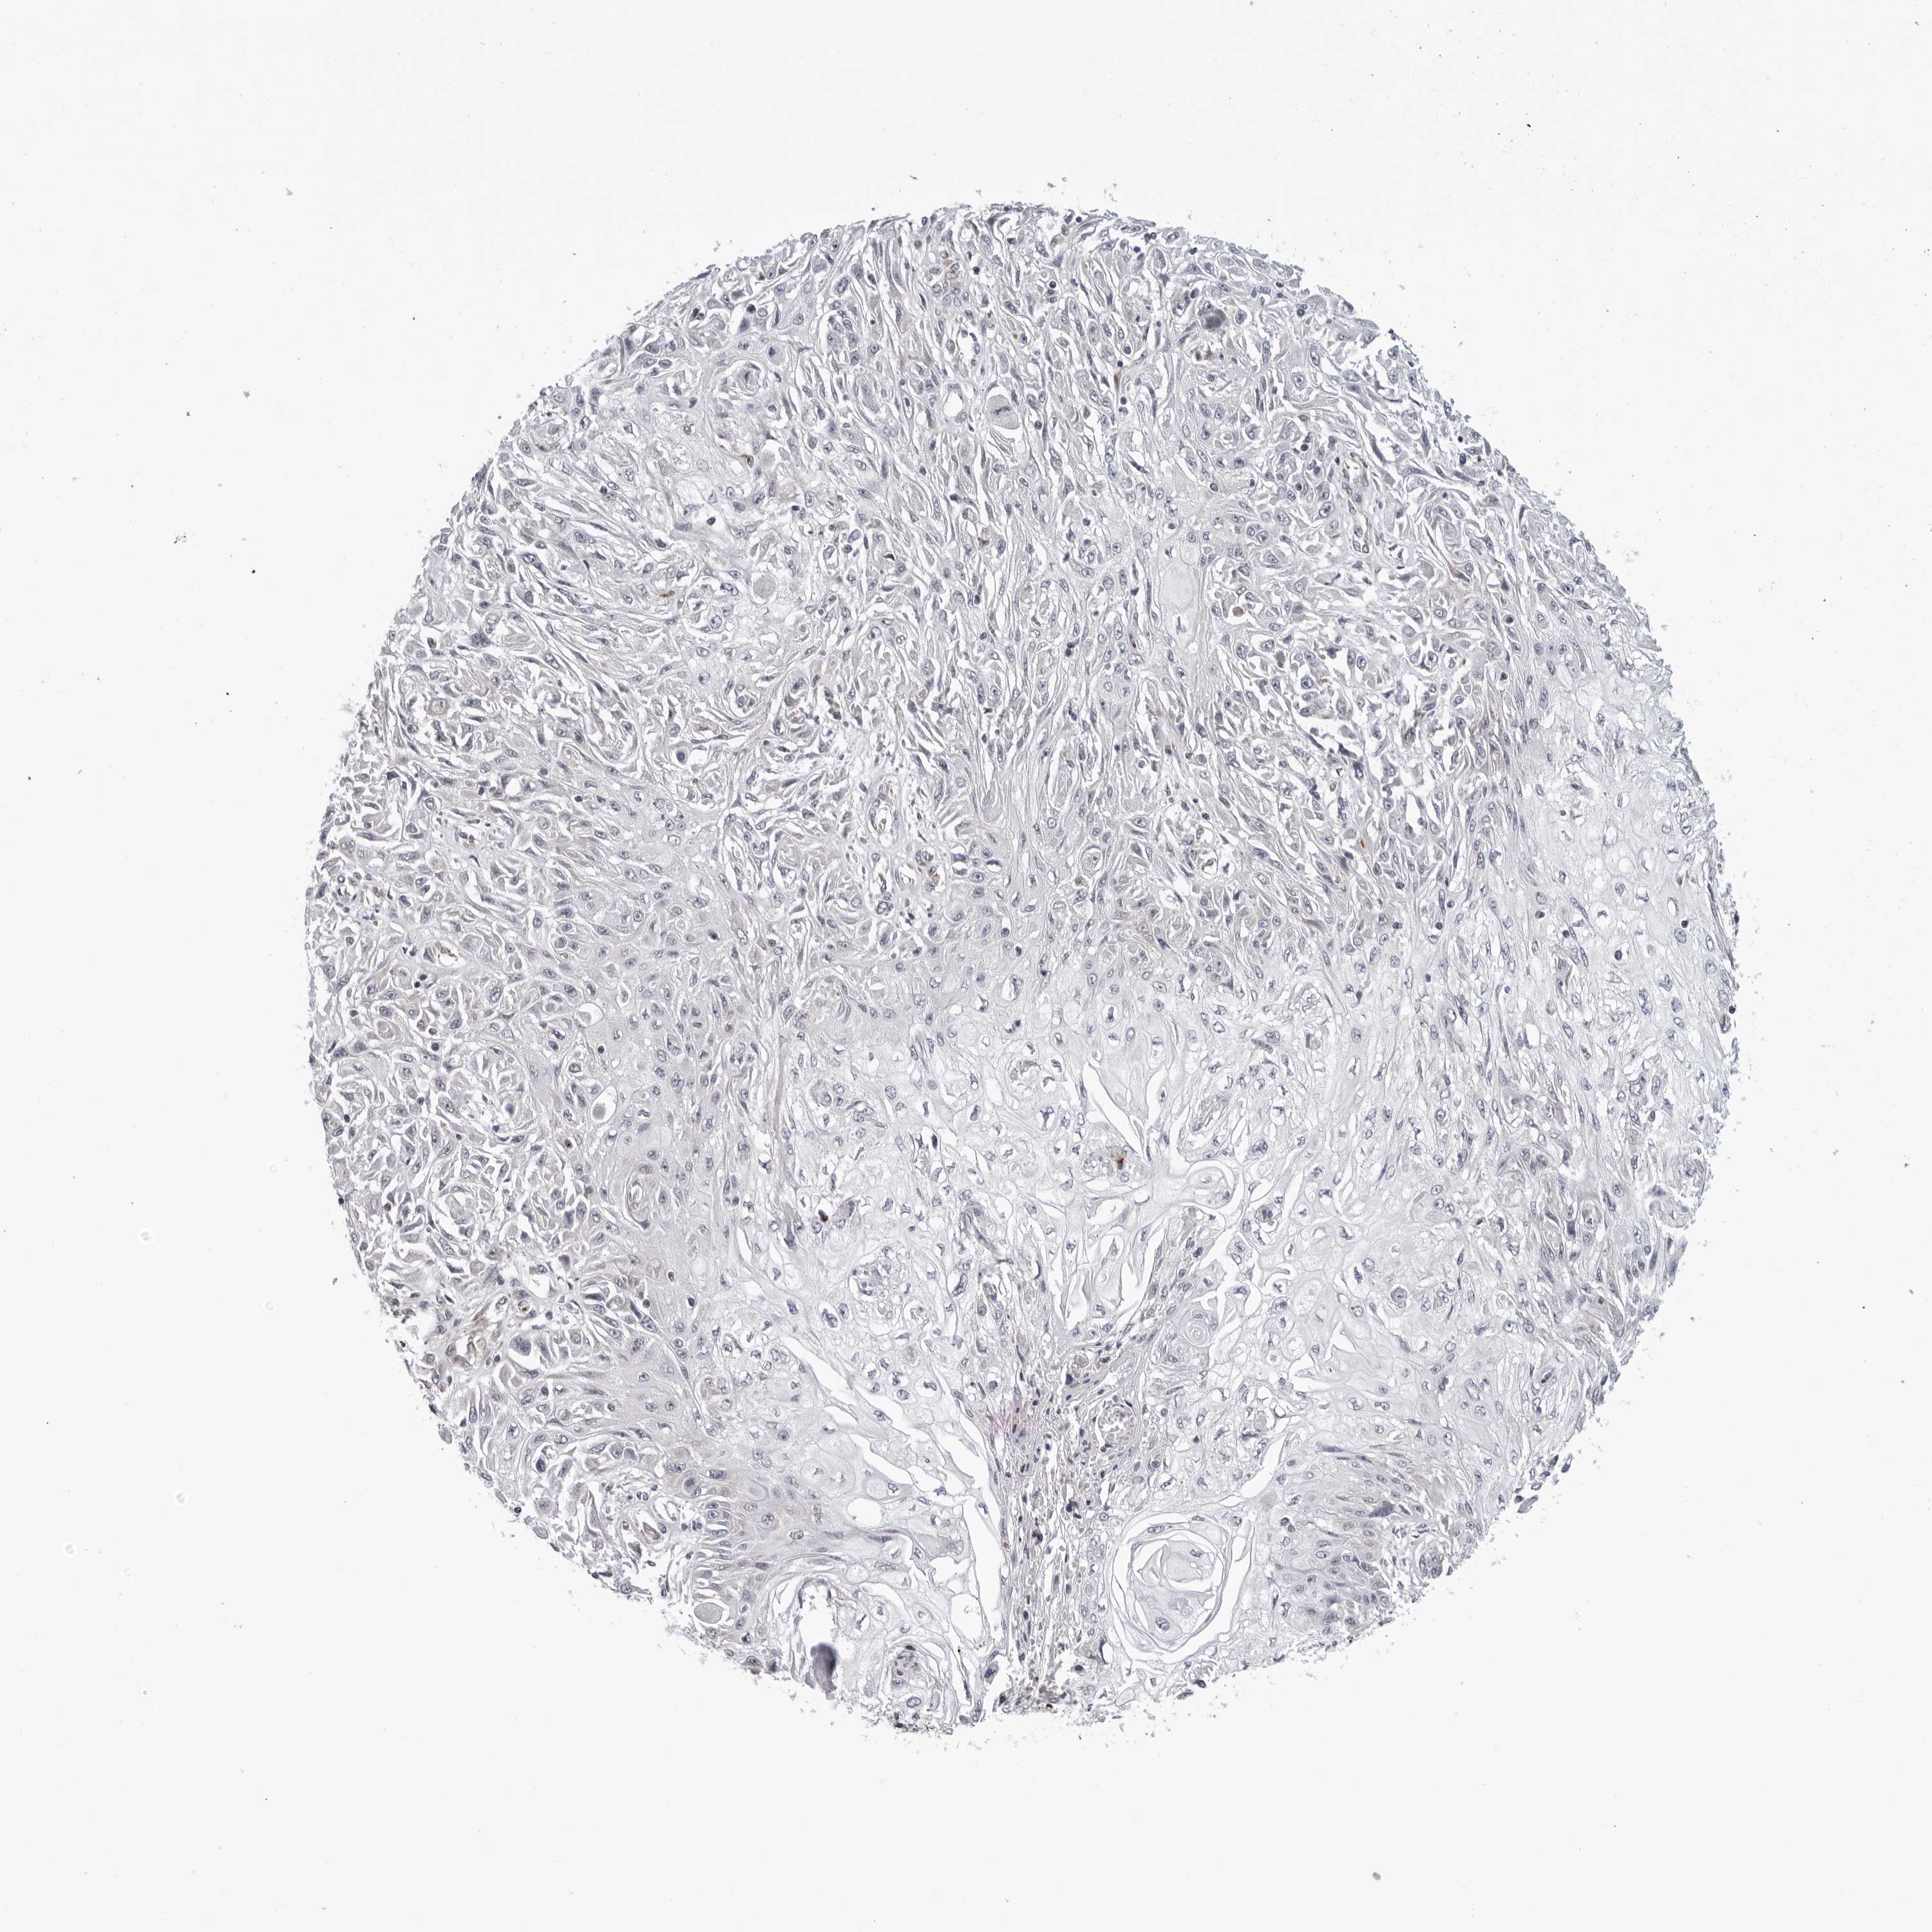

SKIN CANCER - Protein expressioni

A mouse-over function shows sample information and annotation data. Click on an image to view it in a full screen mode. Samples can be filtered based on level of antibody staining by selecting one or several of the following categories: high, medium, low and not detected. The assay and annotation is described here.

Each image is clickable and will lead to virtual microscopy that enables deeper exploration of all samples and also displays staining intensity scores, fraction scores and subcellular localization as well as patient and tissue information for each sample.

Antibody HPA027379

Squamous cell carcinoma, NOS